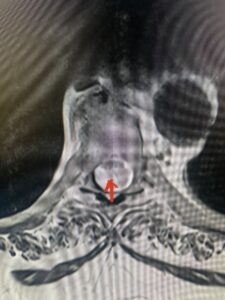

Fig: 2b Axial T2-weighted cervical MRI demonstrating spinal cord compression from C4-5 herniated disc (red arrow)

This 47-year-old male who four months prior was lifting weights developed sharp pain in his neck. After that he developed progressive numbness in his arms, neck pain and headache. He said that the right arm was worse than the left. On examination the patient had long tract weakness on the right side which included his triceps, finger extensors, hip flexors, and dorsiflexors. The patient did not have hyperreflexia. MRI (Fig. 2) demonstrated a massive, extruded disc herniation with severe cord compression. The patient because of progressive myelopathy and spinal cord compression was indicated for anterior cervical discectomy and fusion at C4-5 (Fig. 3). Patient had significant improvement of weakness and numbness post operatively.